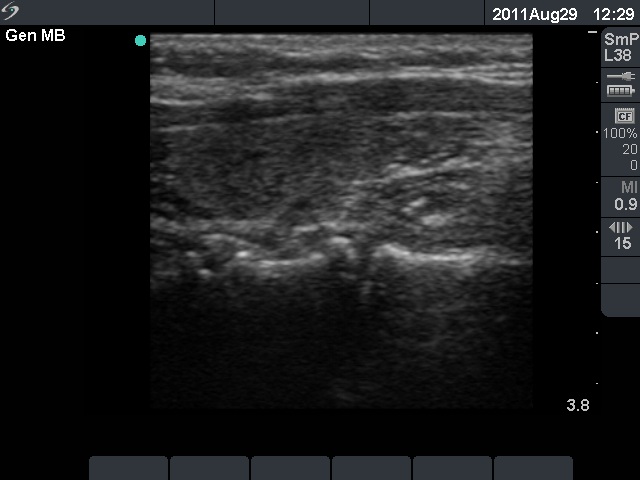

Follow-up examination 3 years later (second row of images):

Ultrasonography: The thyroid was unchanged. The lesions in the dorsal part of the right lobe increased in size and a small hypoechogenic area appeared in the ventral part of the left lobe.

Scintigraphy disclosed parathyroid enlargement not only in the right but even in the left side.

Surgery was performed. Histopathology disclosed hyperplasia of all four parathyroids.